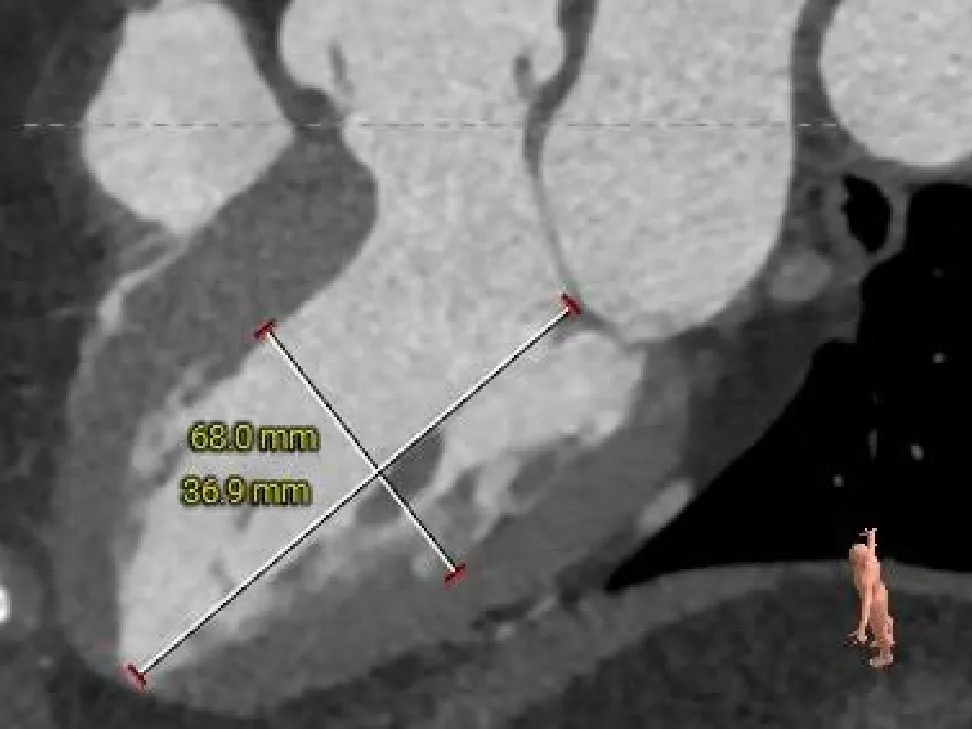

左室测量

术后CT检查

术后CT可见瓣膜展开良好,CA对齐

长轴可见瓣膜位置理想